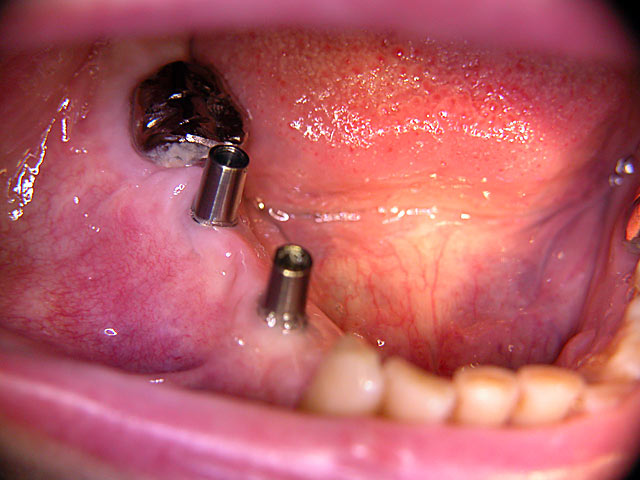

Kurzimplantate und Sofort – Implantate: